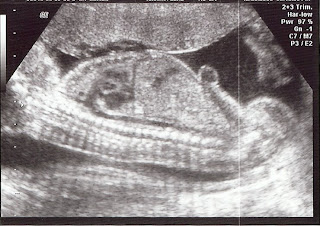

We had another doctor's appointment this week. I am not really sure what I am seeing in a couple of the pictures, but we love the 3-D one! It's little face looks so cute. Richard thinks it has my nose. We were able to see all four chambers of it's heart and watch the blood pump through. He also showed us the brain and other major organs. He said everything looked great!